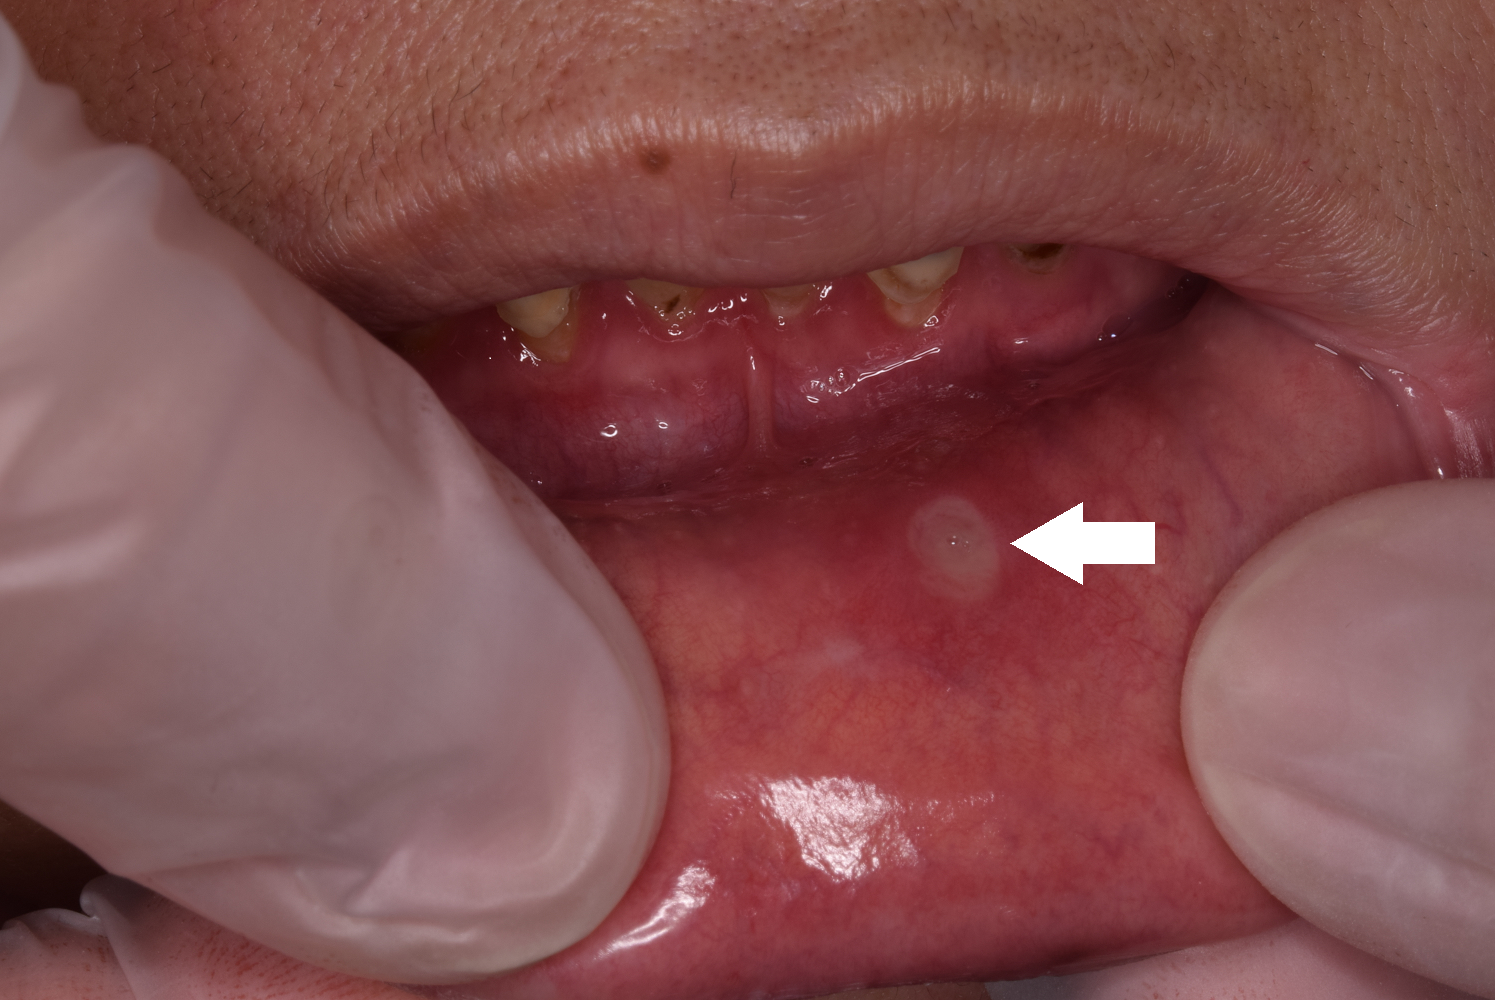

ではお口にはがんはできるのでしょうか?答えは「Yes」です。お口にできるがんを「口腔がん」と呼び、舌、歯肉、口底の順に多くなり、発生する割合はすべてのがんの1~3%とされています。全体として決して多いものではありませんが、近年増加傾向にあります。口腔がんは早期発見できれば治る確立が高いのですが、実際には進行してから発見されることが多く、命に関わることが多くあります。では、どんなことに気をつければ良いのでしょうか?一般的によくある、① 口の中がしみて、痛くて、小さくて白くて、 3、4 日で治るけど、また疲れたりすると出る「口内炎」 は、がんではありません。 (写真1) ただしその逆の、② 痛くなくて、少し幅が広くて、 2 週間以上たっても小さくならず変わらない「口内炎」 はがんに関係する状態「がんもしくは白板症」かもしれません。 (写真2) もし②にあてはまるのであれば、先生に相談してみてください。何事も早期発見が大事になります。

写真2